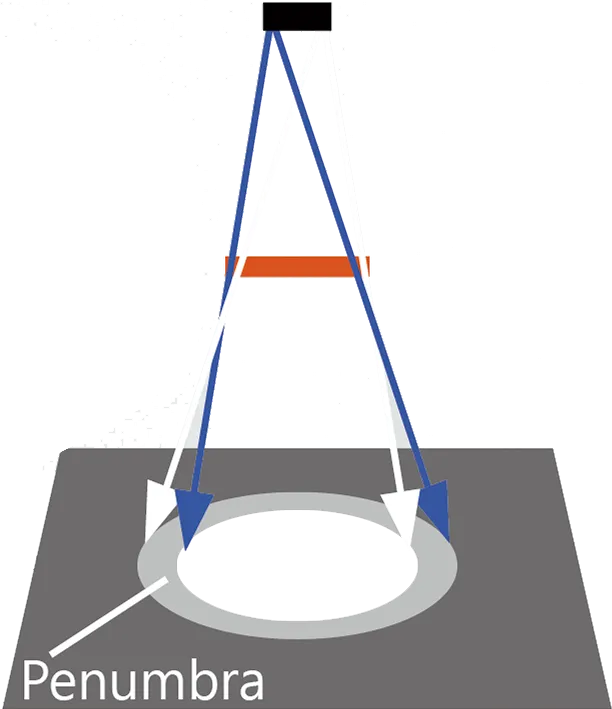

- - Размытые границы - детектор

- - Эффект размера фокального пятна